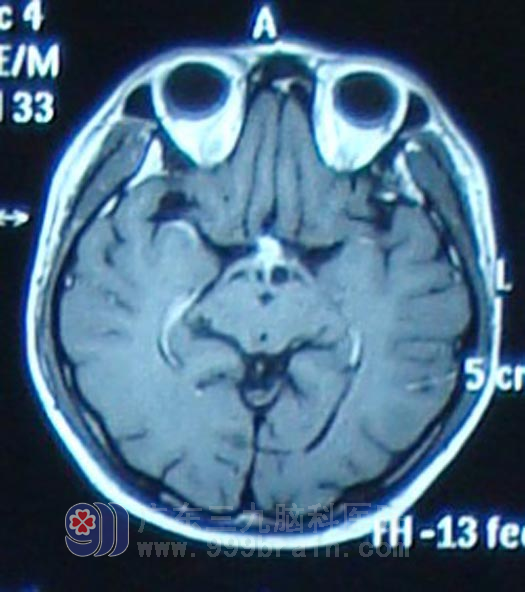

经人介绍,6月20日,小梁在家人陪同下来到广东三九脑科医院肿瘤综合治疗中心就诊。该中心蔡林波主任在了解小梁病史时发现,他除了视力下降(左眼视力0.1,右眼视力0.2)、视野发生改变外(双眼颞侧及上下侧视野缺损),近2个月以来还出现了多饮多尿现象,结合其影像学资料,蔡林波主任高度怀疑小梁患的是生殖细胞瘤,但确诊仍需要更多的临床资料。于是,抽取小梁的脑脊液进行化验检查,结果示HCG(人绒毛膜促性腺激素)值高出正常值10多倍,AFP(甲胎蛋白)也高于正常,这进一步证明小梁所患脑瘤为生殖细胞瘤的可能性极大。鉴于生殖细胞瘤首选放射治疗,蔡林波主任首先为小梁制定了定位适形诊断性放疗方案,放疗10Gy后,复查头颅MR显示肿物较前明显缩小,确诊为生殖细胞瘤。遂开始予全脑全脊髓放疗,完成54Gy后复查头颅MR显示肿瘤基本消失。患者症状明显改善,多饮多尿症状减轻,患者左眼视力恢复至0.4,右眼视力0.5。

放疗结束后